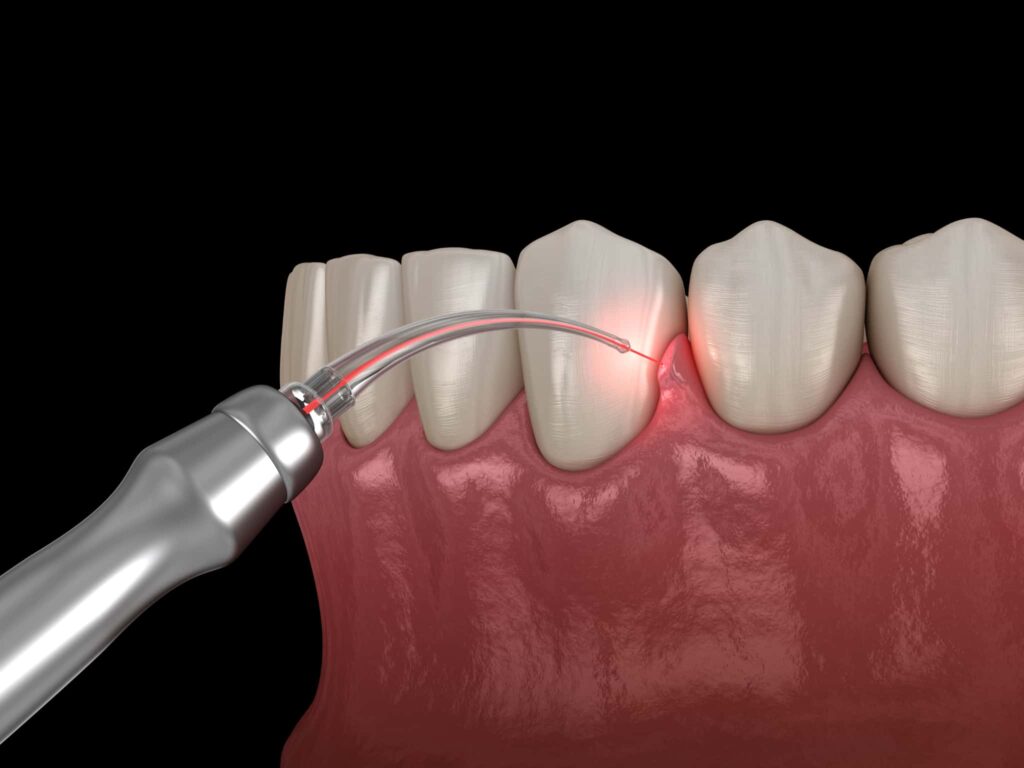

レーザー治療

歯周ポケット内の細菌除去や組織の殺菌を目的に、レーザーを使用する方法もあります。出血が少なく痛みも抑えられるため、患者の負担が小さいのが特徴です。レーザー照射により歯周ポケットの状態が改善するとともに、同時に歯ぐきの引き締め効果も期待できます。